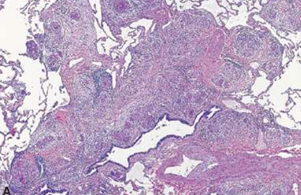

Sarcoidosis